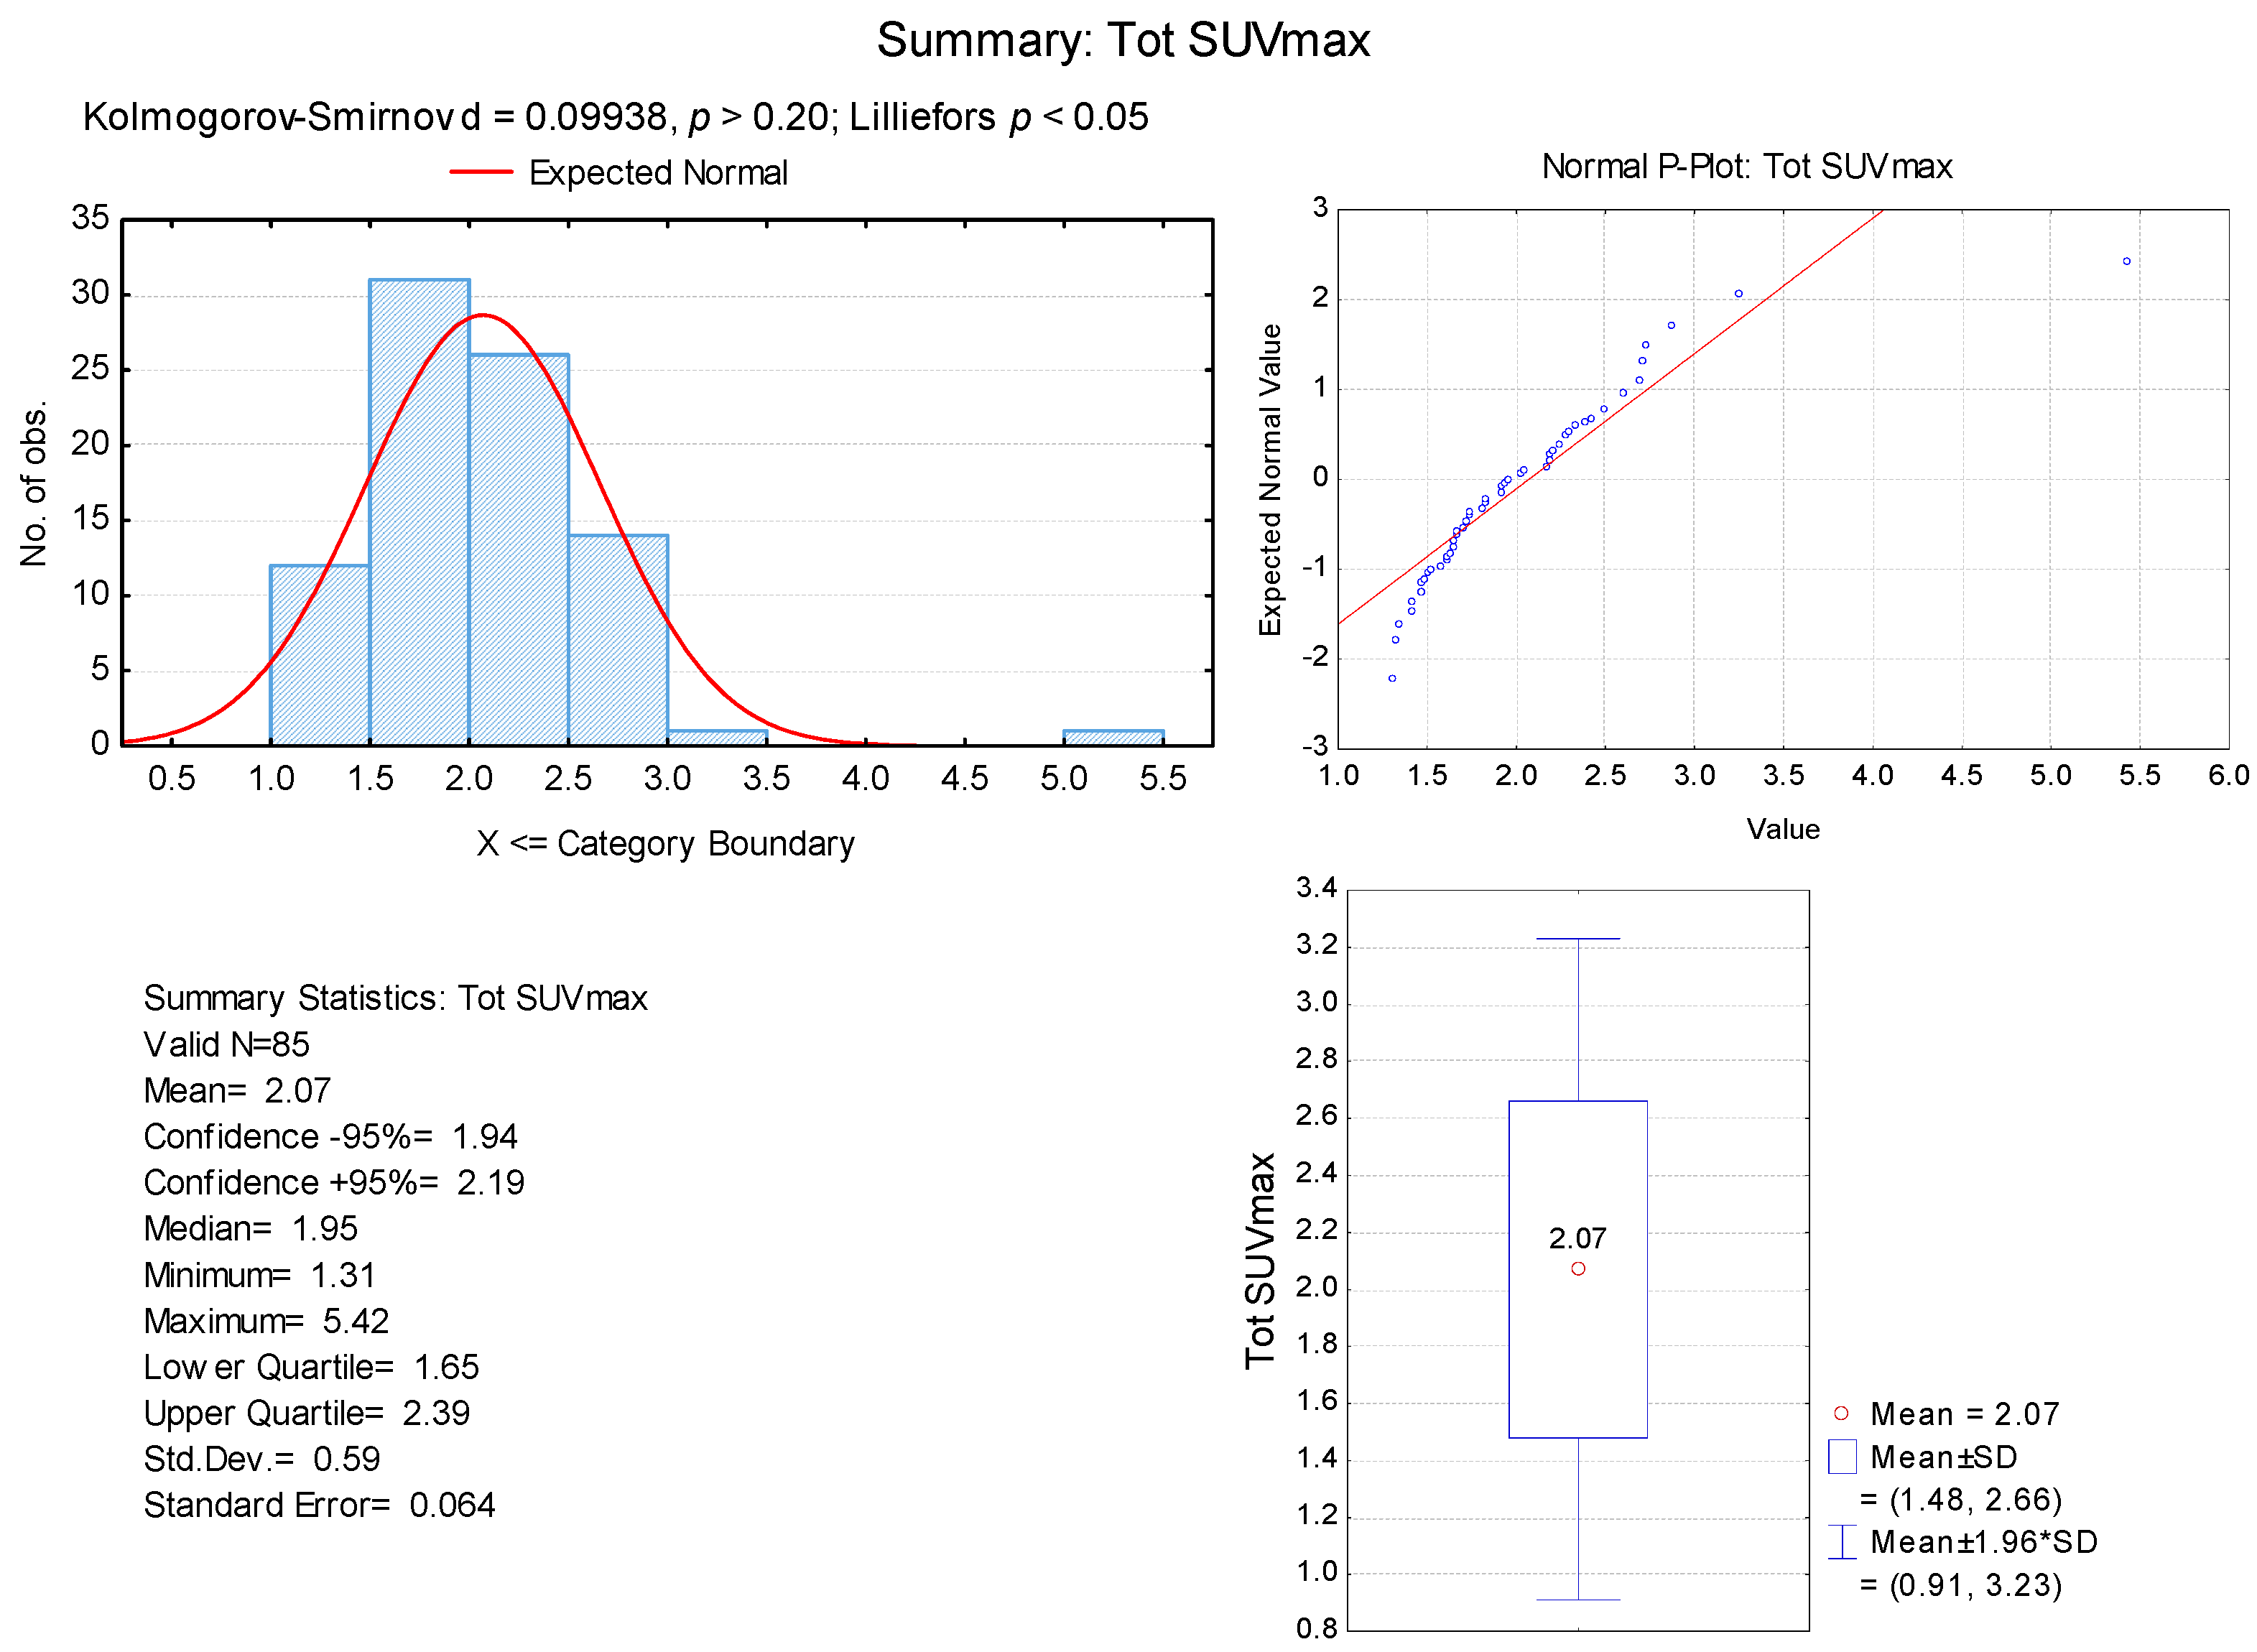

3. Results